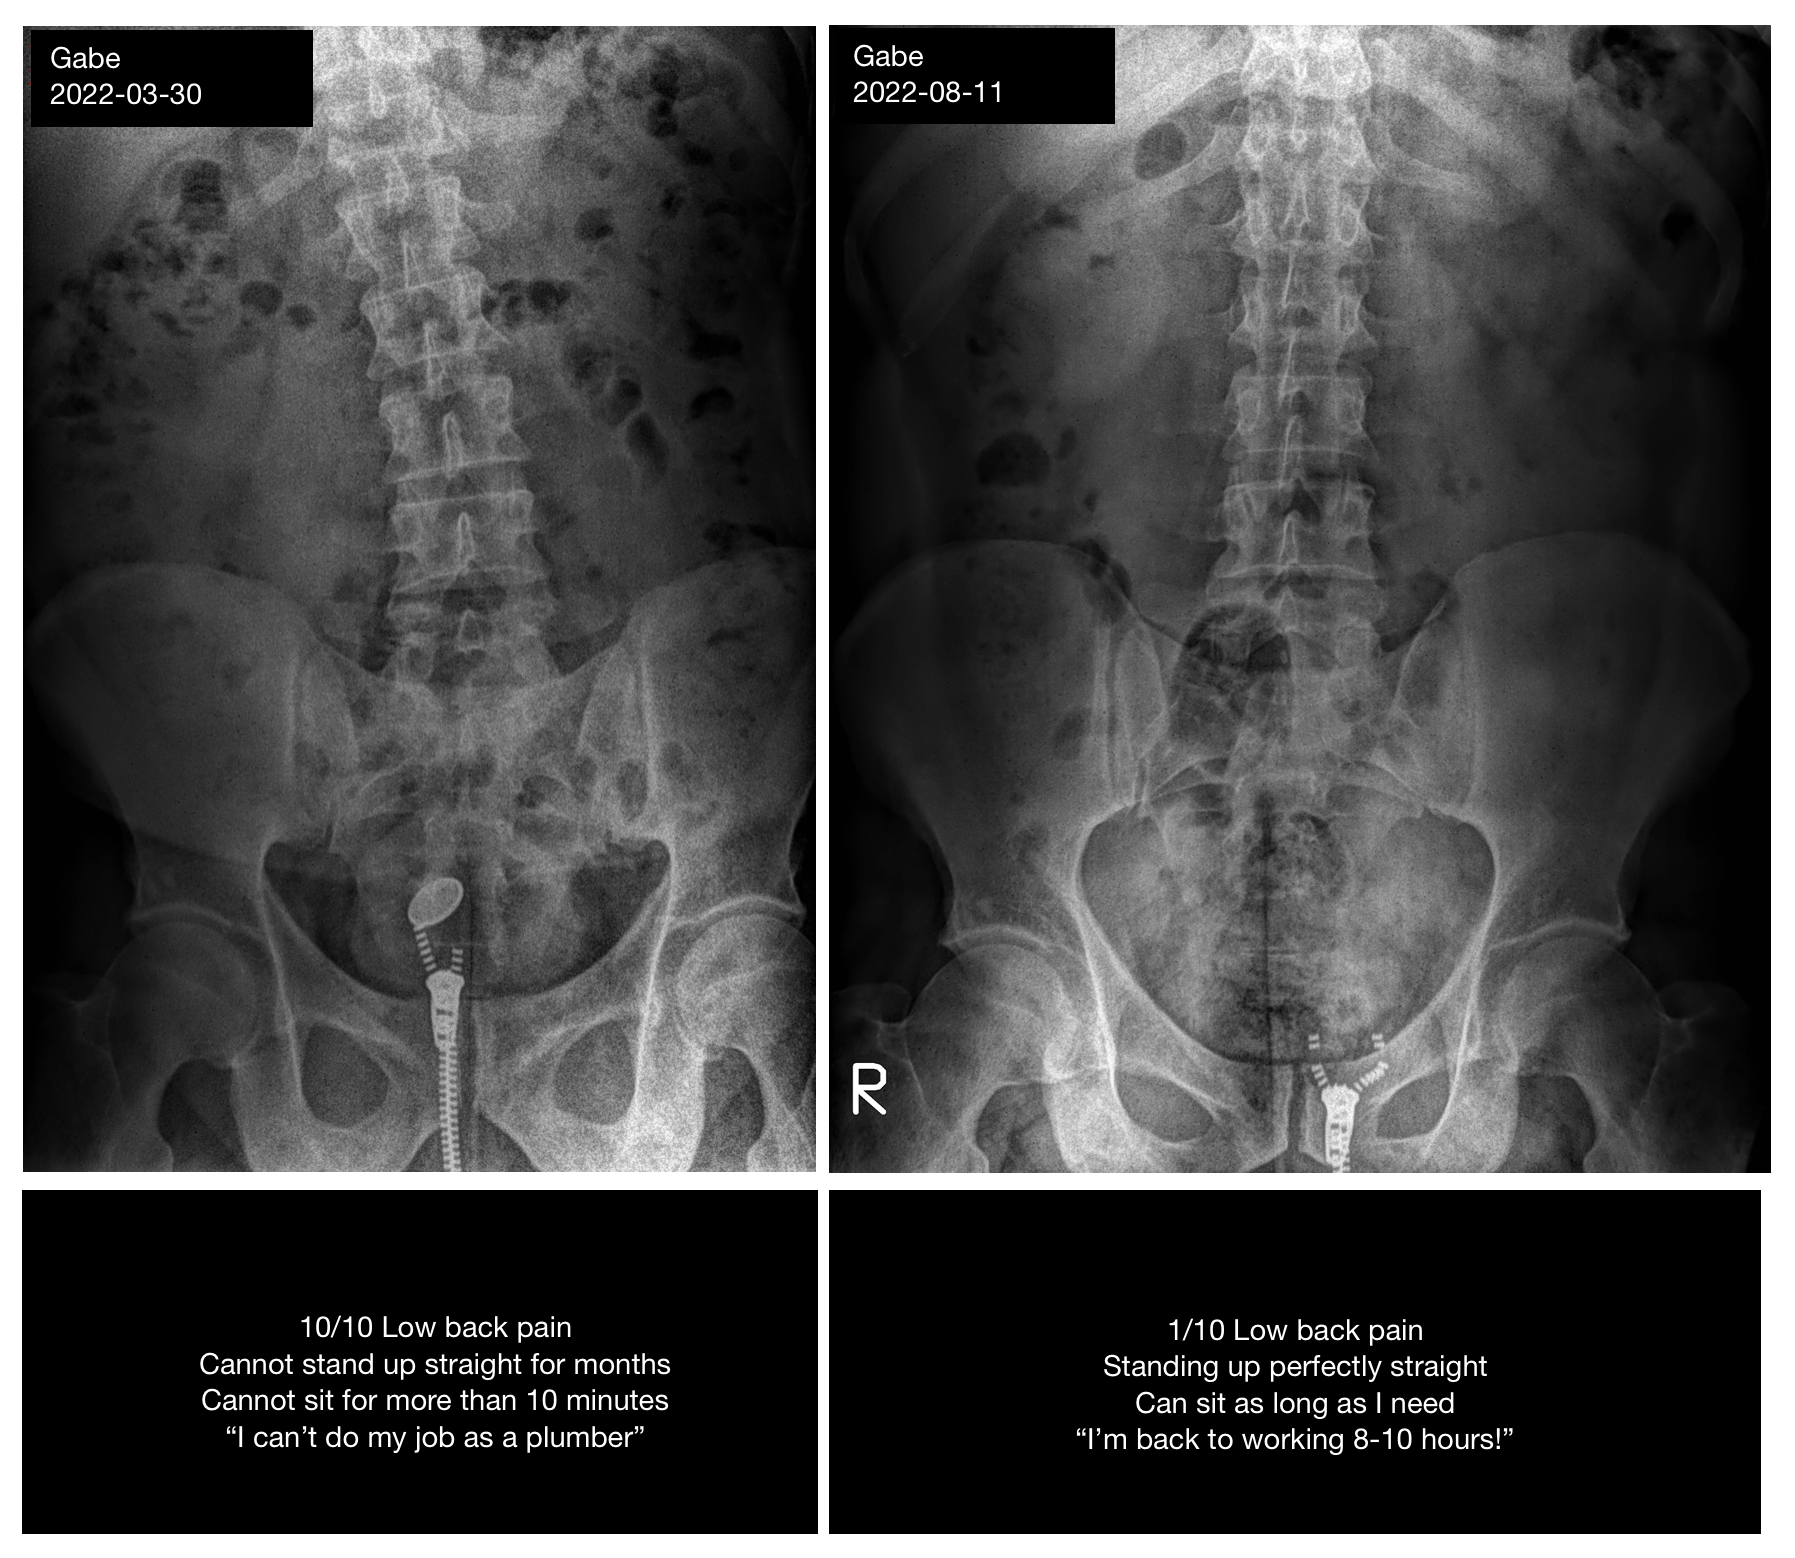

Pain went from 10/10 to 1/10 in ~5 months. Couldn't stand straight or sit >10 min. Now back to working 8-10 hours as a plumber.